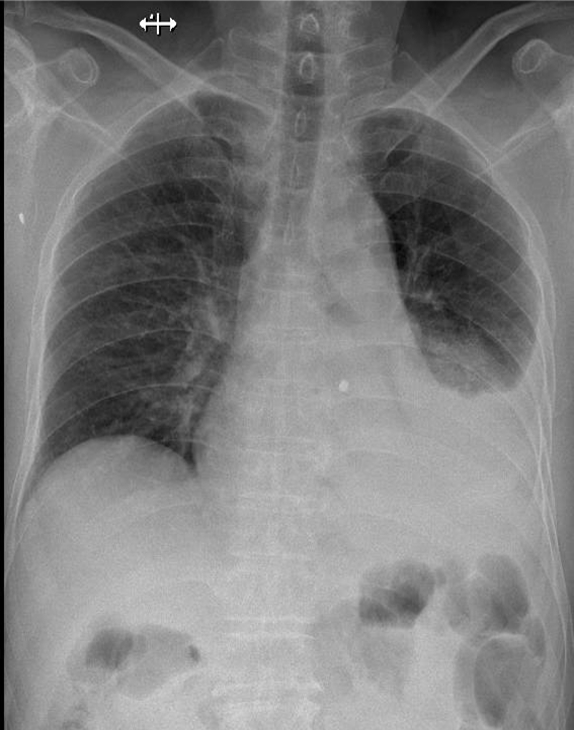

Hãy phân tích tình huống NỮ 86 tuổi -CĐ:tràn dịch màng phổi trái nghi do lao màng phổi (cđpb: K phổi), cao huyết áp

1-Thâm nhiễm phế nang thùy dưới phổi (T) => Viêm phổi 2-Tràn dịch màng phổi (T) lượng trung bình